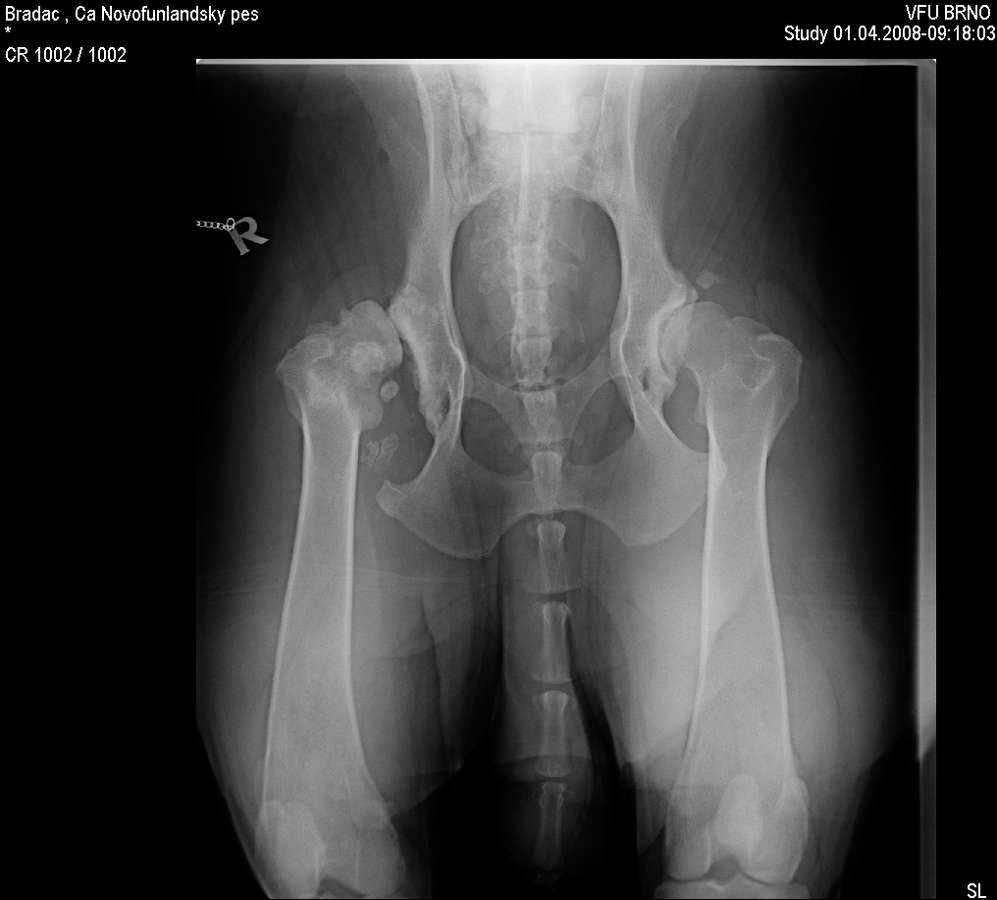

Znovu na rentgenu jsme byli ve zhruba čtyřech letech, kdy Grif prodělal amputaci plovací blány, protože se mu po zánětu udělala boule velikosti velkého vlašského ořechu. Rentgen, který zde vidíte je poslední, ze skoro sedmi let, kdy jsme byli na operaci s předním loktem, artrózu bylo nutné odfrézovat. Ano, to byla poslední zatím neoperovaná noha. Pro přehled je vedle další rentgen zdravého psa (mladého leonbergera). Prohlédněte si oba klouby. (Kliknutím otevřete obrázky v plné velikosti).